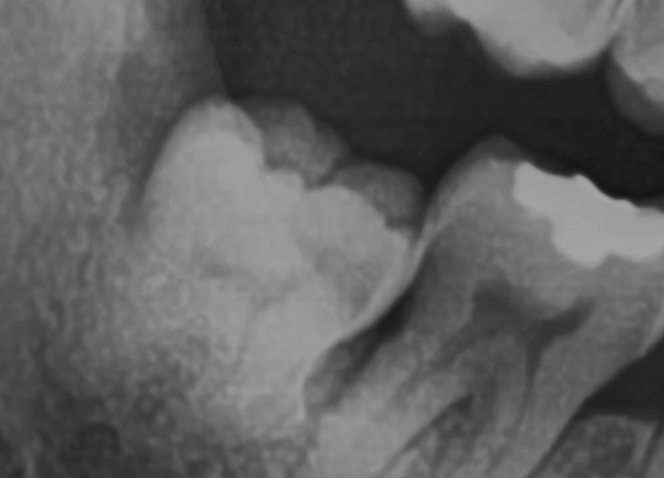

2) 복잡매복: 아래 사진을 보면 사랑니가 누워있어, 그냥 뽑을 수 없는 것을 복잡매복이라 하고, 마취를 하고, 사랑니 일부를 절단한 후에 뽑는다고 하네요.

3) 완전매복: 잇몸 밖으로 나오지 않은 사랑니를 완전매복이라 하며, 앞치아에 영향이 없다면 뽑을 필요가 없을 수 있지만, 앞치아의 뿌리를 누르는 등 영향을 주고 있다면 잇몸을 절개하여 발치합니다.